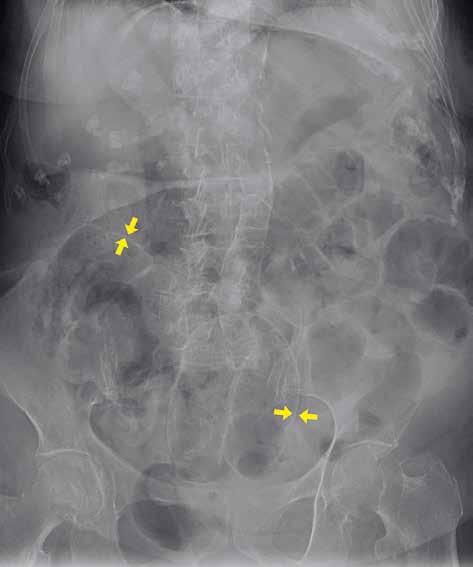

Volný vzduch v peritoneální dutině je většinou známkou patologické komunikace trávicí trubice s volnou dutinou břišní (obr. 4). Pravidelně ho vídáme po břišních operacích, zejména po laparoskopii. U prostého snímku břicha horizontálním paprskem je centrální paprsek zaměřen do středu spojnice hřebenů lopat kyčelních, a subdiafragmatický prostor je tak zobrazen zespodu šikmo, a ne tangenciálně. Výsledkem je superpozice s masou celých jater a sumace především s dorzálním diafragmatickým recesem, vyplněným vzdušnou plicní tkání. Větší diagnostický význam při detekci plynu pod bránicí má proto prostý snímek hrudníku vestoje. Volný plyn je detekovatelný i na snímku břicha vleže na zádech (znamení dvojité stěny – „double wall“ sign) (obr. 5). Malé množství volného plynu v dutině břišní je však takto nezobrazitelné. Také srůsty mohou bránit migraci plynu do podbráničních prostor, a tím zvyšovat falešnou negativitu vyšetření. Nejčastějšími příčinami pneumoperitonea jsou perforace trávicí trubice (vředová choroba gastroduodenální, komplikovaná divertikulitida, traumatické či iatrogenní příčiny). Kromě trávicí trubice

Obr. 5: RTG snímek břicha vleže. Pneumoperitoneum. Žluté šipky označují místa, na kterých je střevní stěna ohraničena jednak plynem v lumen střeva, jednak volným plynem v okolí. 1